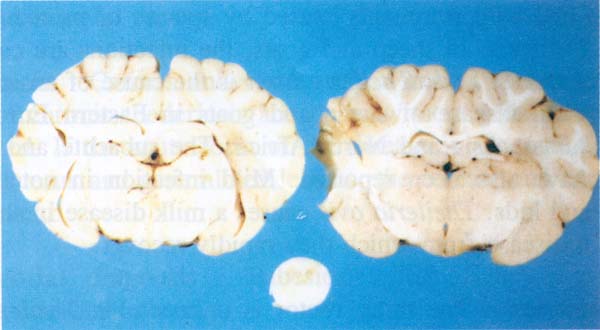

- Beyindeki ince duvarlı kist (Şekil 167)

Şekil 167 : Coenurus cerebralis. Beyindeki ince duvarlı kist.